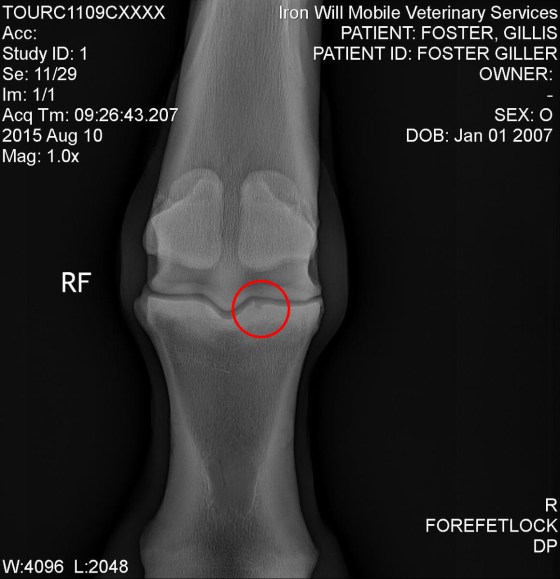

This is the first bone chip we discovered, and though it looks like it is located at the front of the fetlock, the x-ray doesn’t show depth, so surgery will show us exactly where it lies. Before going into surgery, the surgeon thought this was the one likely causing the most trauma, because you can see it is perfectly positioned to really tear up the cartilage in that joint. It may also be trying to form a cyst. Lovely.